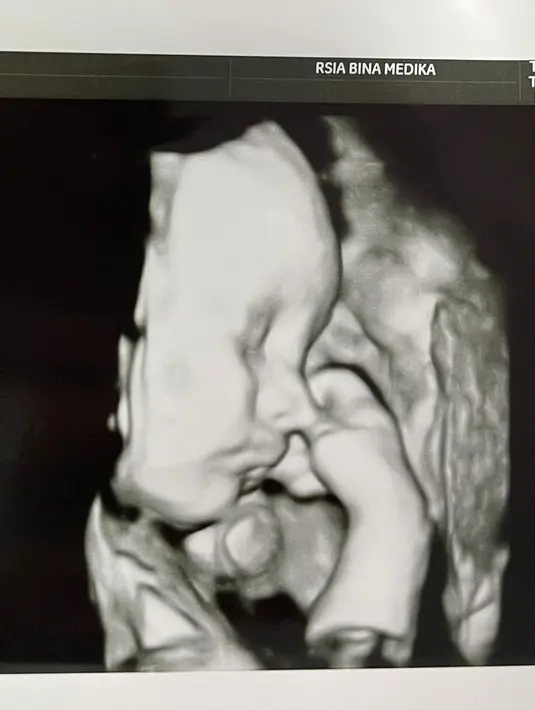

Seperti diberitakan sebelumnya, Audy Marissa melahirkan anaknya di usia 31 minggu atau sekitar delapan bulan. Anthoni Xie pun masih tidak tega melihat bayinya yang lahir secara prematur tersebut. (Instagram/anthonyxie_)

"Sekarang mungkin belum kelihatan seperti bayi lainnya, tapi yang aku lihat dia kecil banget, nggak tega aja. Dia kan kecil banget ya aku udah lihat hidungnya mirip Audy, ada mirip aku juga, Sama lah ya," paparnya.